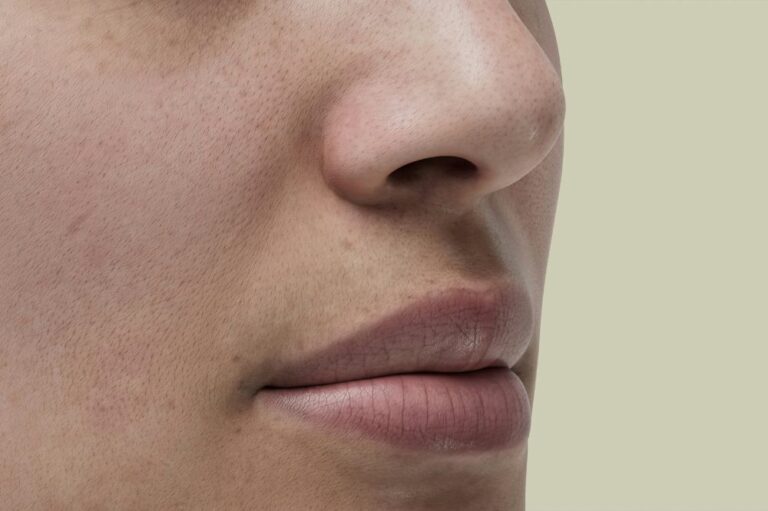

Receding gums are usually a sign of gum disease (including gingivitis and periodontitis) and are typically not reversible.

Cold sores are contagious fever blisters that usually occur outside the mouth while canker sores are non-contagious blisters that happen inside the mouth.